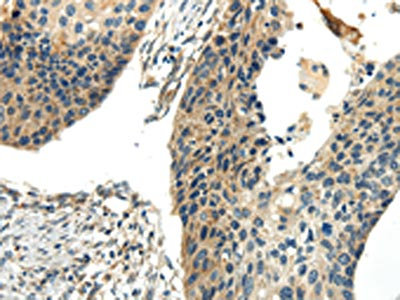

The image on the left is immunohistochemistry of paraffin-embedded Human liver cancer tissue using CSB-PA910897(CHGB Antibody) at dilution 1/30, on the right is treated with synthetic peptide. (Original magnification: ×200)

The image on the left is immunohistochemistry of paraffin-embedded Human esophagus cancer tissue using CSB-PA910897(CHGB Antibody) at dilution 1/30, on the right is treated with synthetic peptide. (Original magnification: ×200)